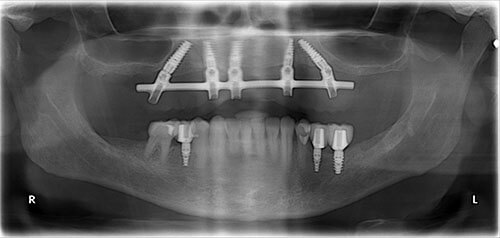

After after all on 4 x-ray view female patient case 1

after all on 4 x-ray view female patient case 1

Male

Dr. Cavaretta